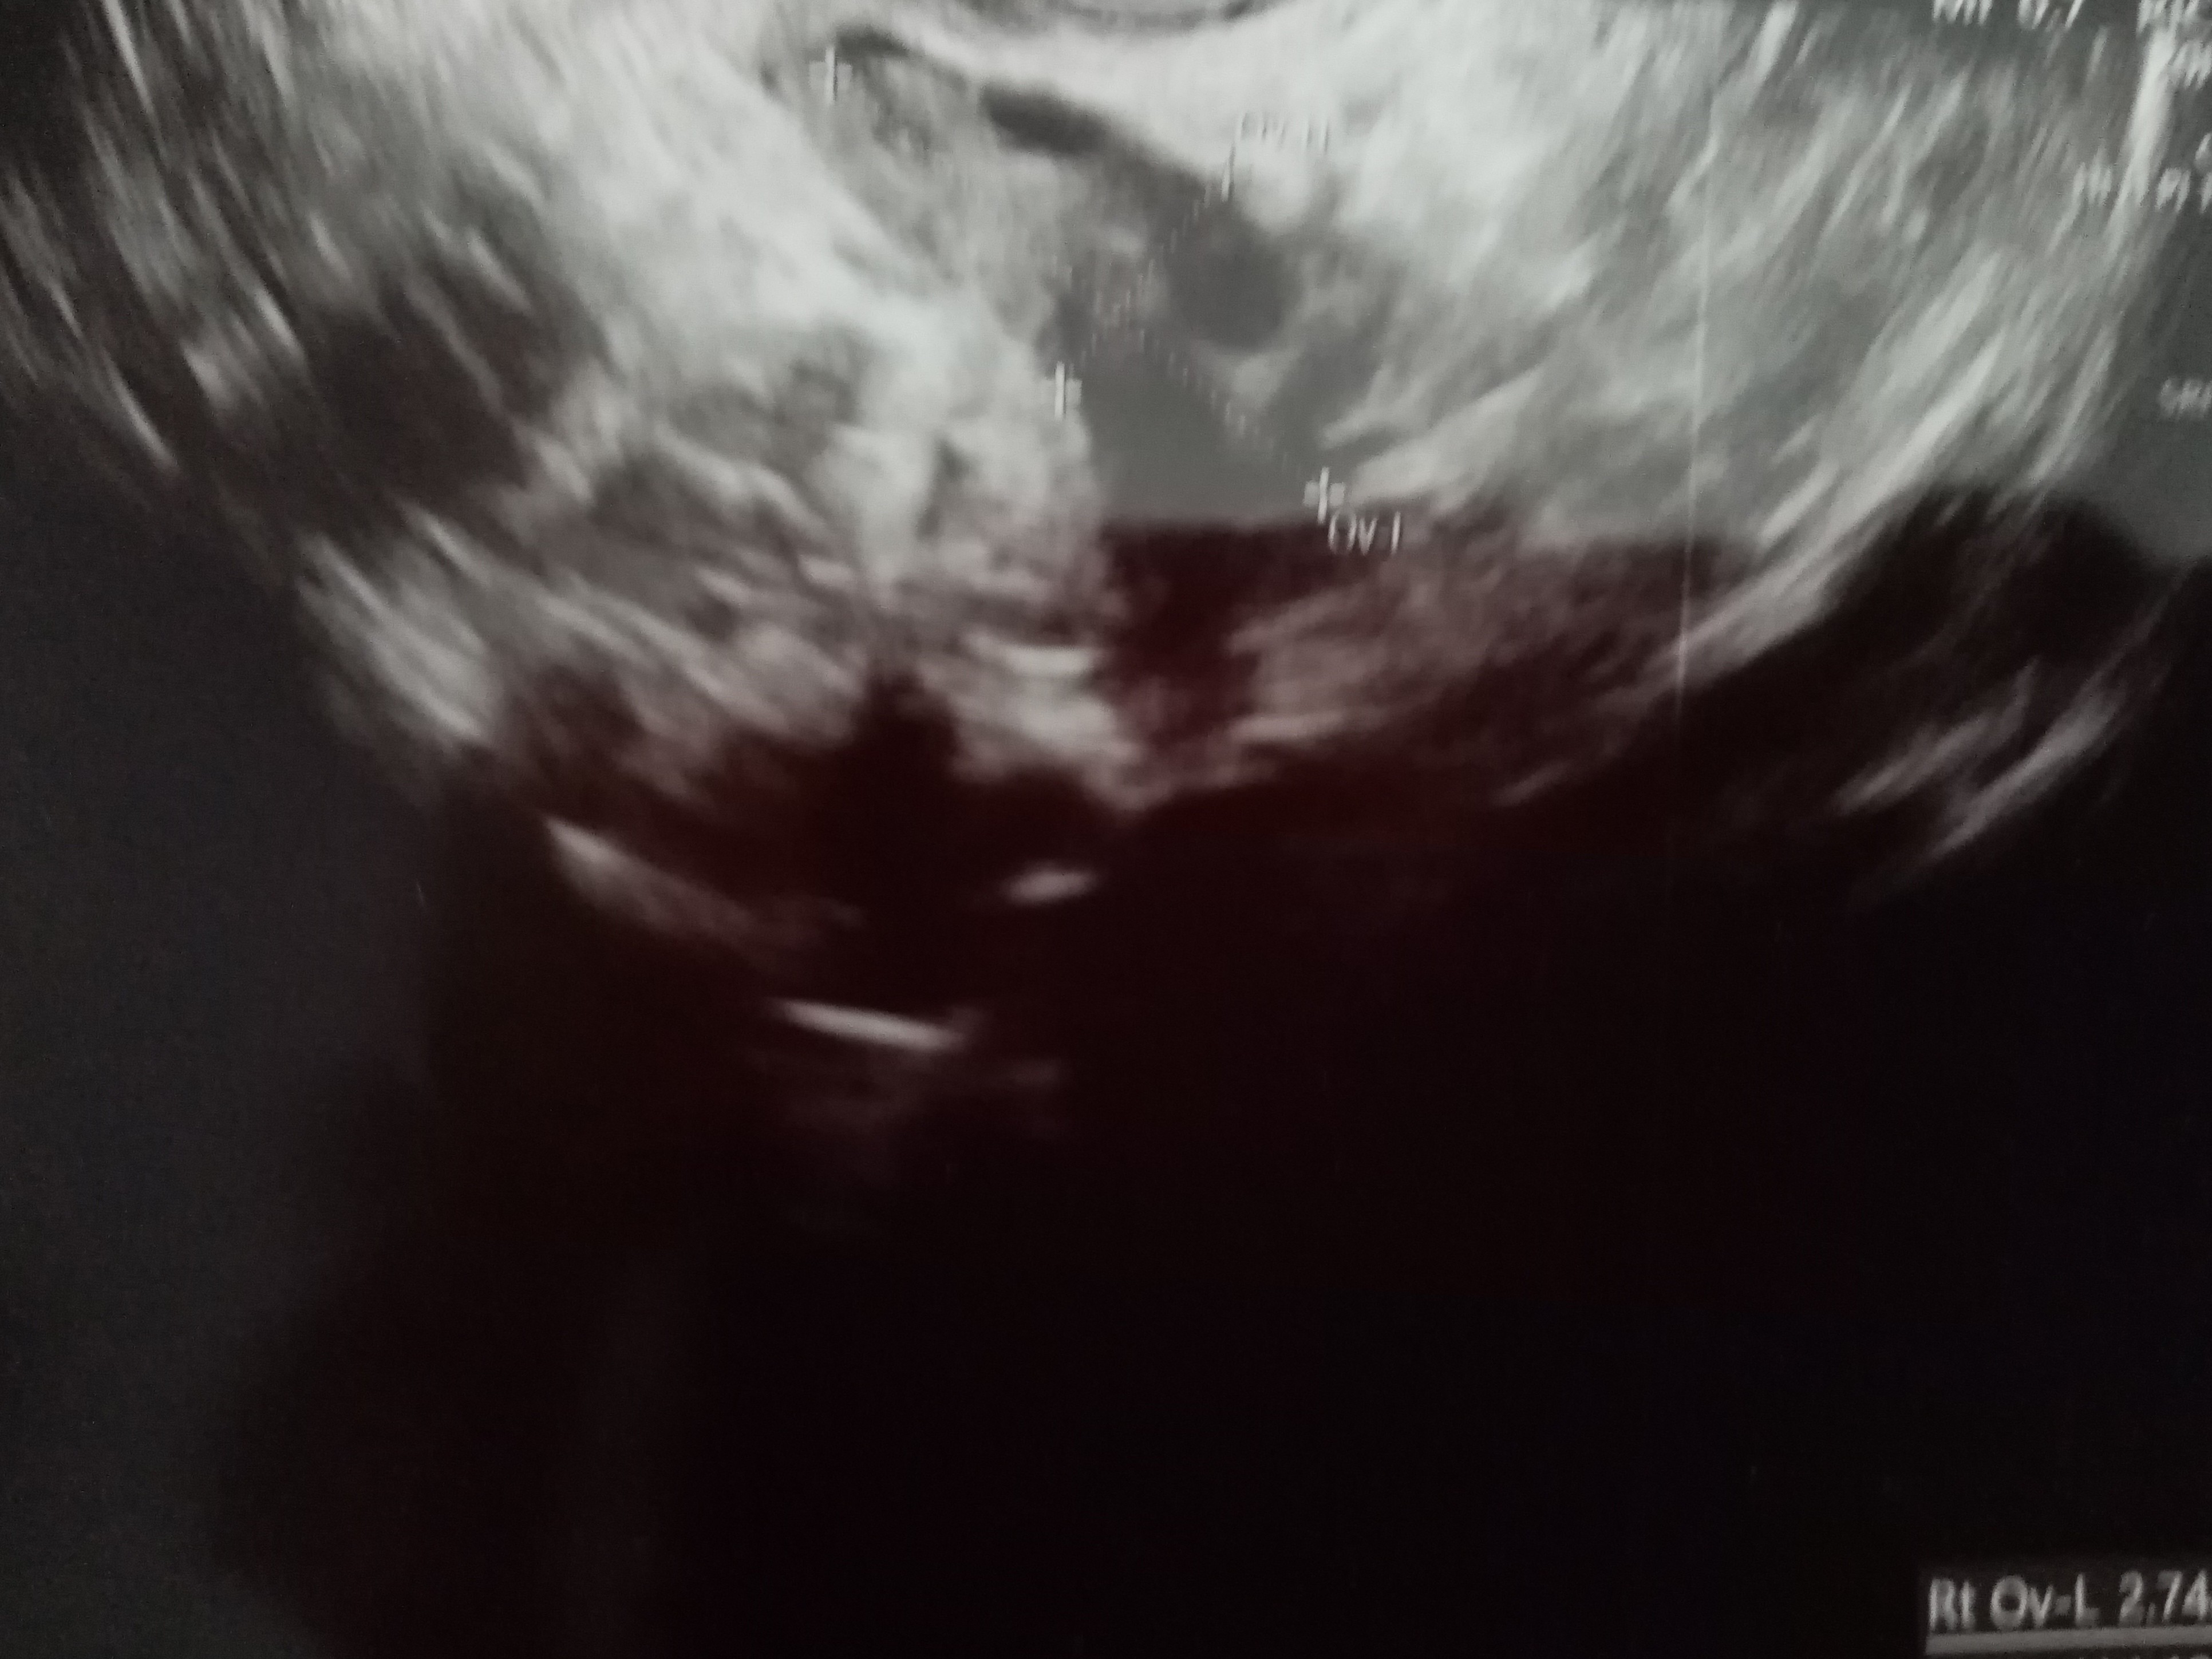

Dziewczyny byłam dzisiaj prywatnie na wizycie. Pęcherzyk jest w macicy i większy niż 2 dni temu ale bez ciałka żółtego . Ma 5mm. Jutro wyniki bety i progesteronu. Wklejam zdjęcia. Co sądzicie?

• IMG_20210617_172703.jpg

IMG_20210617_172703.jpg

1,5 MB · Wyświetleń: 83